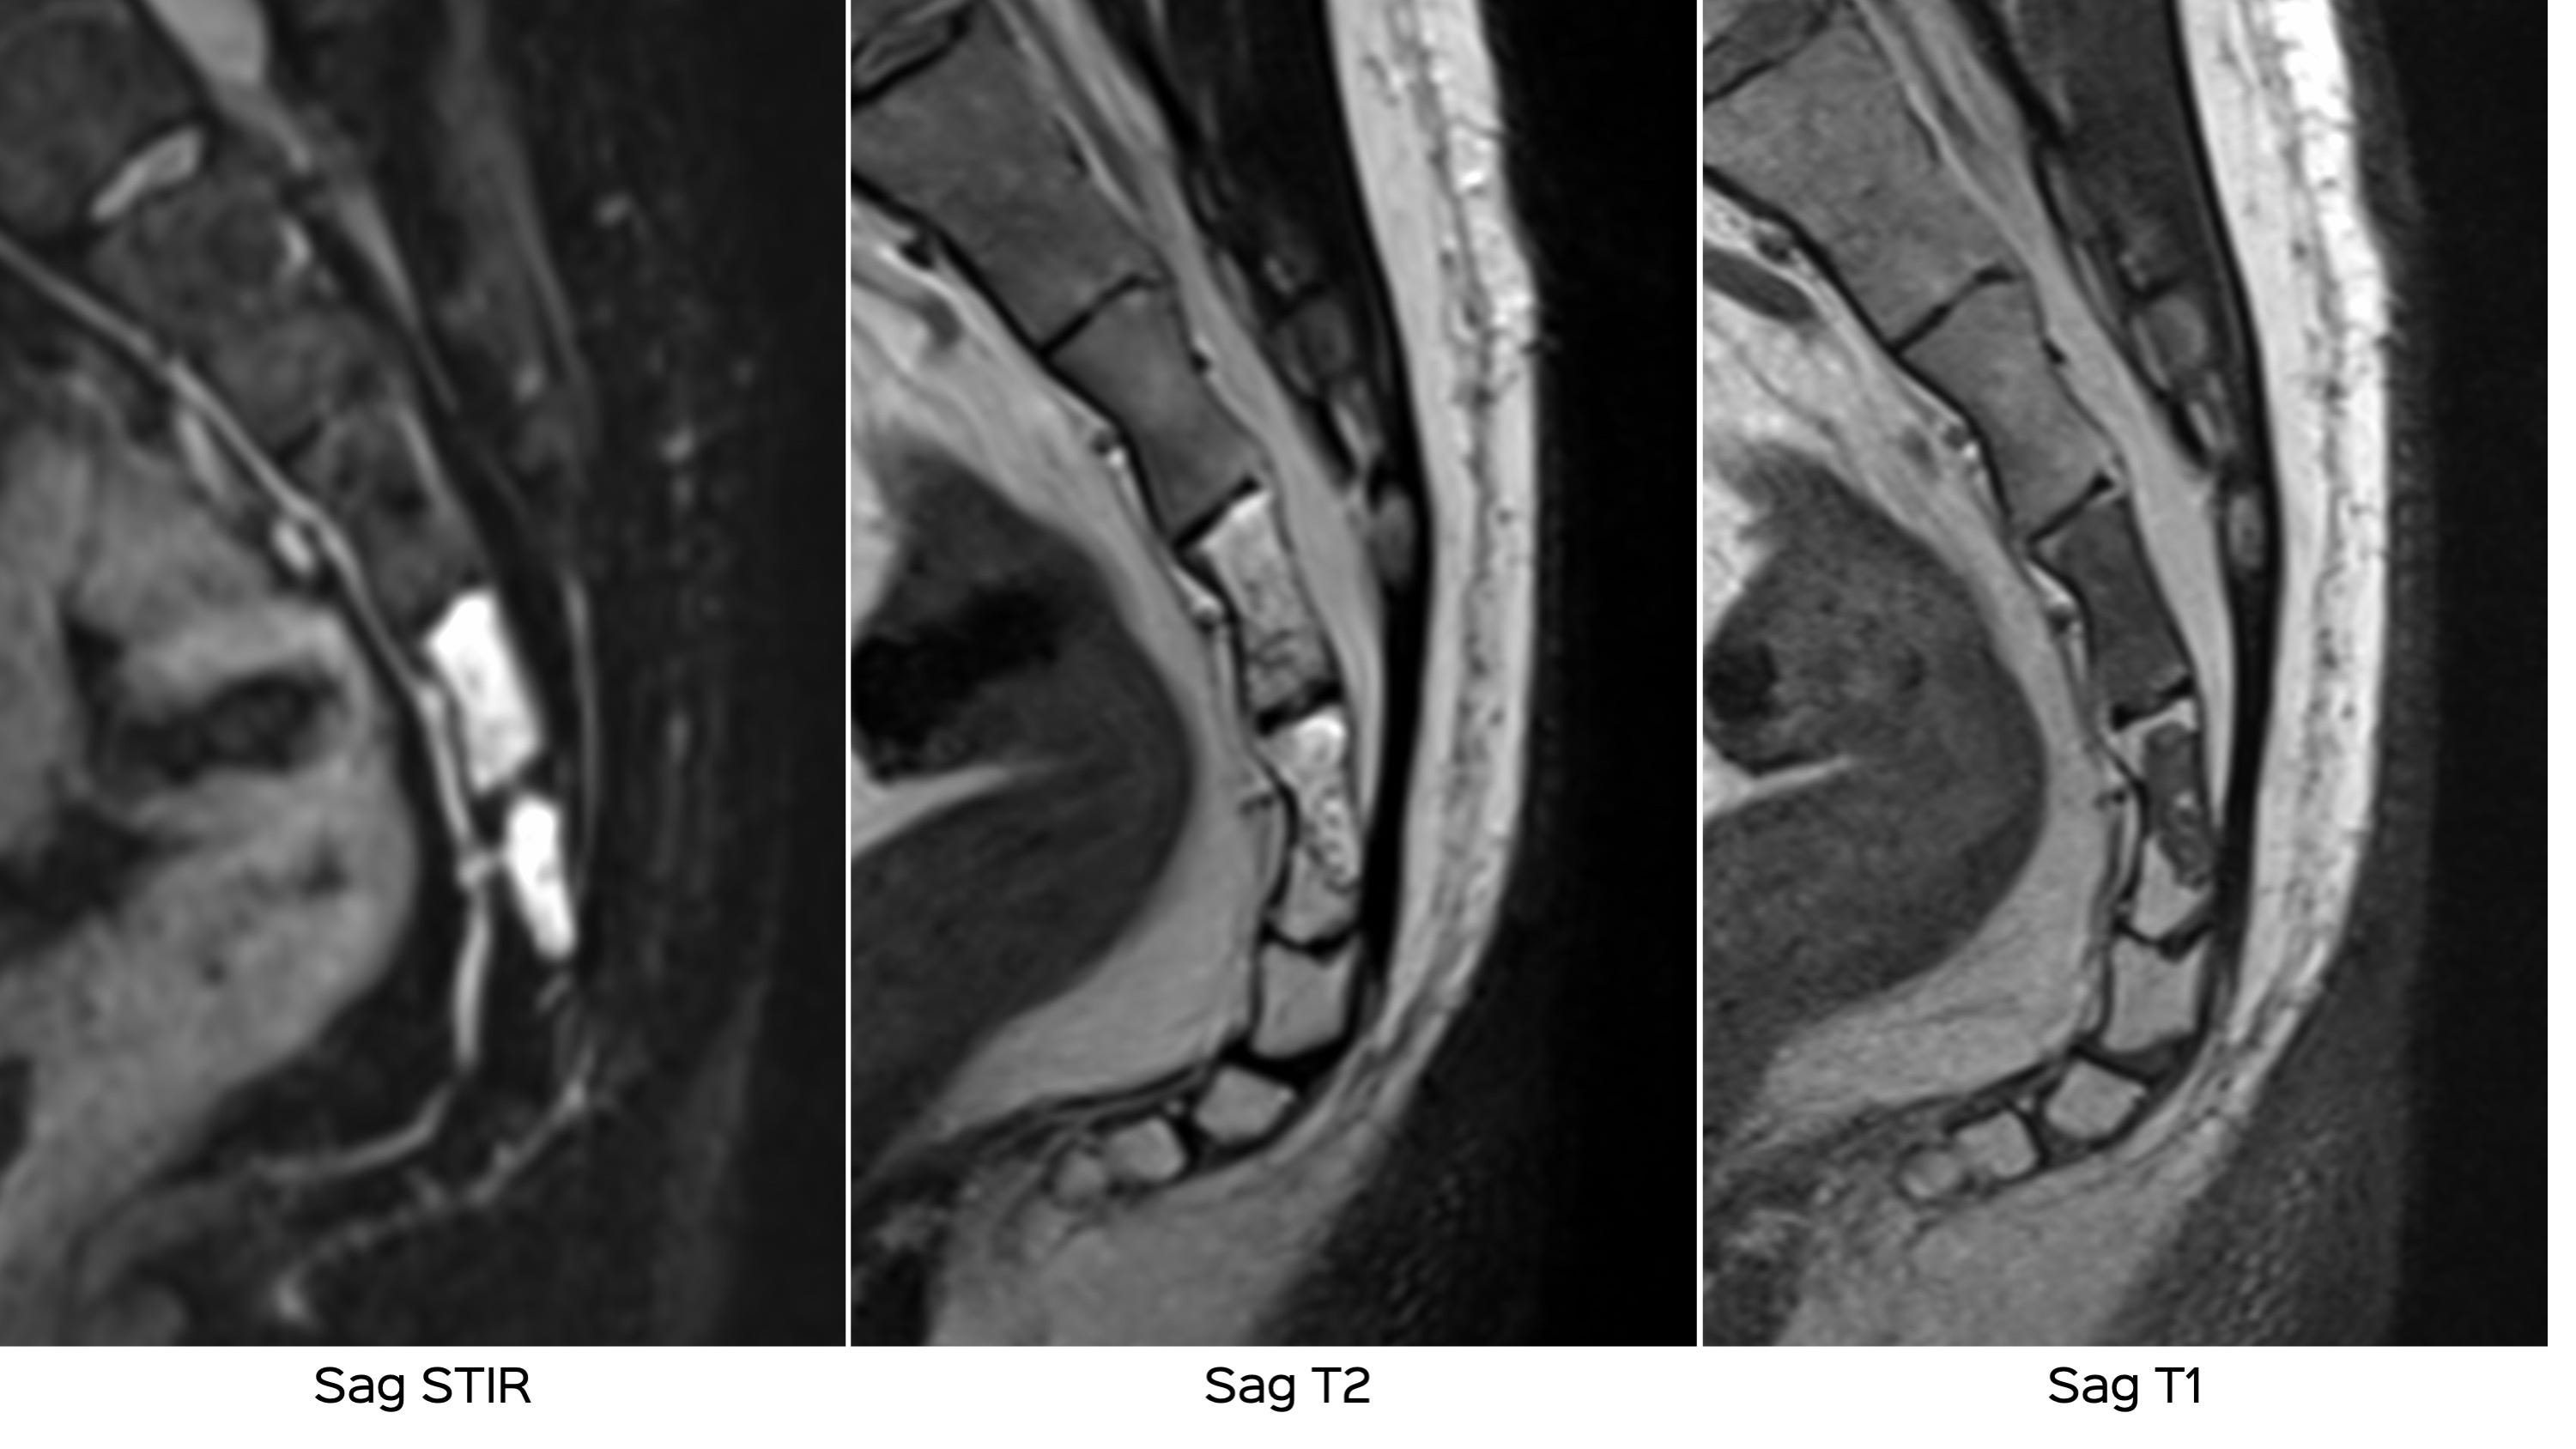

This 51-years old presented with erratic coccygeal pain. The MRI showed these findings.

The patient’s symptoms and MRI did not match. A PET/CT was then done for further work-up.